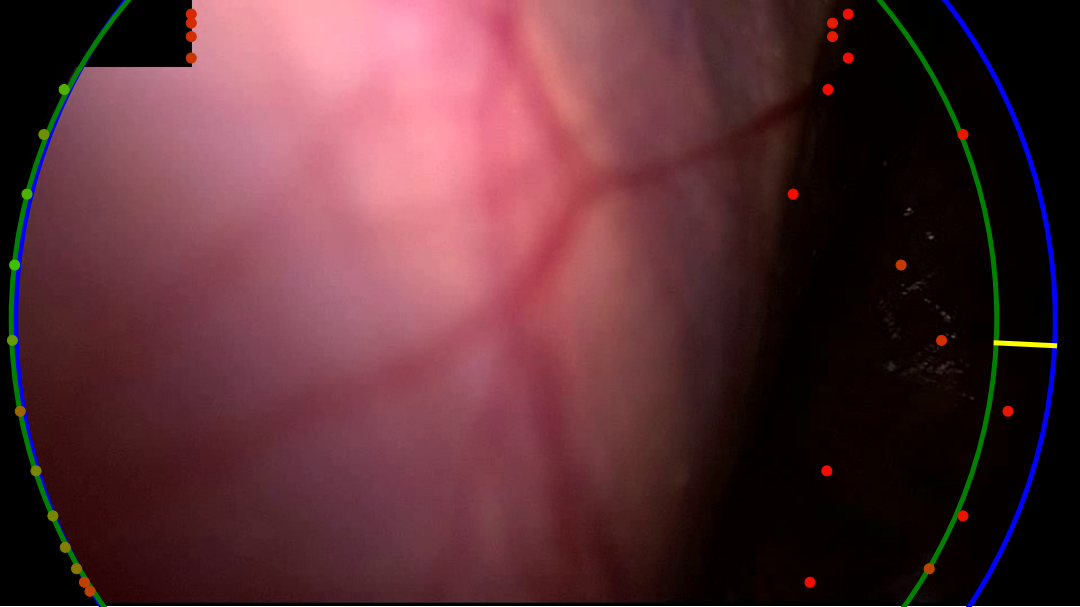

Refer to caption

(a) The dark right-hand side of the content area is missed by both variants. The learned variant gets a slightly better fit, this could be due to a better positioing of points on the left-hand side of the content area.

(b) A noisy and bright border poses a challenge for the handcrafted variant. Too few edge points are detected to make a confident estimate of the circle. The learned variant manages to correctly identify the right-hand edge of the content area, however, the circle fits to incorrect edge points found on the blacked out secondary video feed in the top-left.

(c) Both variants correctly identify the edge in the bottom-left but mistake dark regions in the top-right and bottom-right corners as border regions. The learned variant rejects the final circle as the circle score is too low. This scenario, where a single corner of the image is outside the content area, features prominantly in our failure cases.

(d) In this sample, the handcrafted variant detects edge points in the bottom-left, but scores them poorly. The circle fitting then chooses the incorrectly identified edge points in the top-left. The learned variant scores the detected points in the bottom-left higher, and so the circle fitting finds a satisfying result.

Figure 6: A selection of failure cases of our algorithm taken from the RobustECA dataset, the results of both the handcrafted (left) and learned (right) variants are shown for each image. The edge of the ground truth and inferred circular image projections are shown in blue, and green, respectively. Points indicate the position of detected edge points, the colour of each point indicates its score, going from red to green as the score increases. The vector found when calculating the Hausdorff distance is shown in yellow.